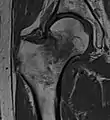

في الحالات التي يشتبه في وجود كسر الورك ولكنه ليس واضح على الأشعة السينية، الاشعة المقطعية ثلاثية الابعاد (3D reconstruction) تكون مفيده للتشخيص. وقد اكتسب التصوير بالرنين المغناطيسي أهمية في تشخيص الحالات الغامضه من كسور رقبة عظمة الفخذ. في غضون 24 ساعة يمكن للتغييرات أن تري في التصوير بالرنين المغناطيسي. مسح العظام هو أقل فائدة لأنه قد يستغرق ما يصل إلى الاسبوع لإظهار التغيرات وخاصة في كبار السن.

كسور عنق الفخذ يحدث في العنق الضيق بين الرأس الدائريه لعظمة الفخذ وجسم العظمة. هذا الكسر في كثير من الأحيان يعطل وصول الدم إلى رأس عظم الفخذ.